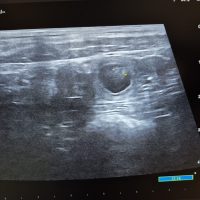

Update 31.07.2025: Wir waren beim Ultraschall und Namaari ist tragend!

Die Geburt begann am 10.09.2025 absolut perfekt, wie aus dem Lehrbuch. Einer nach dem anderen erblickte das Licht der Welt, bis Welpe Nummer 9 geboren war. Dann stockte die Geburt. Ein Röntgenbild zeigte, dass noch drei Welpen unterwegs waren, doch der anschließende Ultraschall brachte traurige Nachrichten: Einer der Welpen hatte es leider nicht geschafft und blockierte den Weg für die anderen beiden. Ein Kaiserschnitt war unvermeidlich.